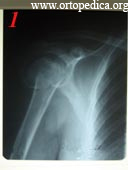

2. Больная М. Состояние после однопольсного эндопротезирования правого плечевого сустава